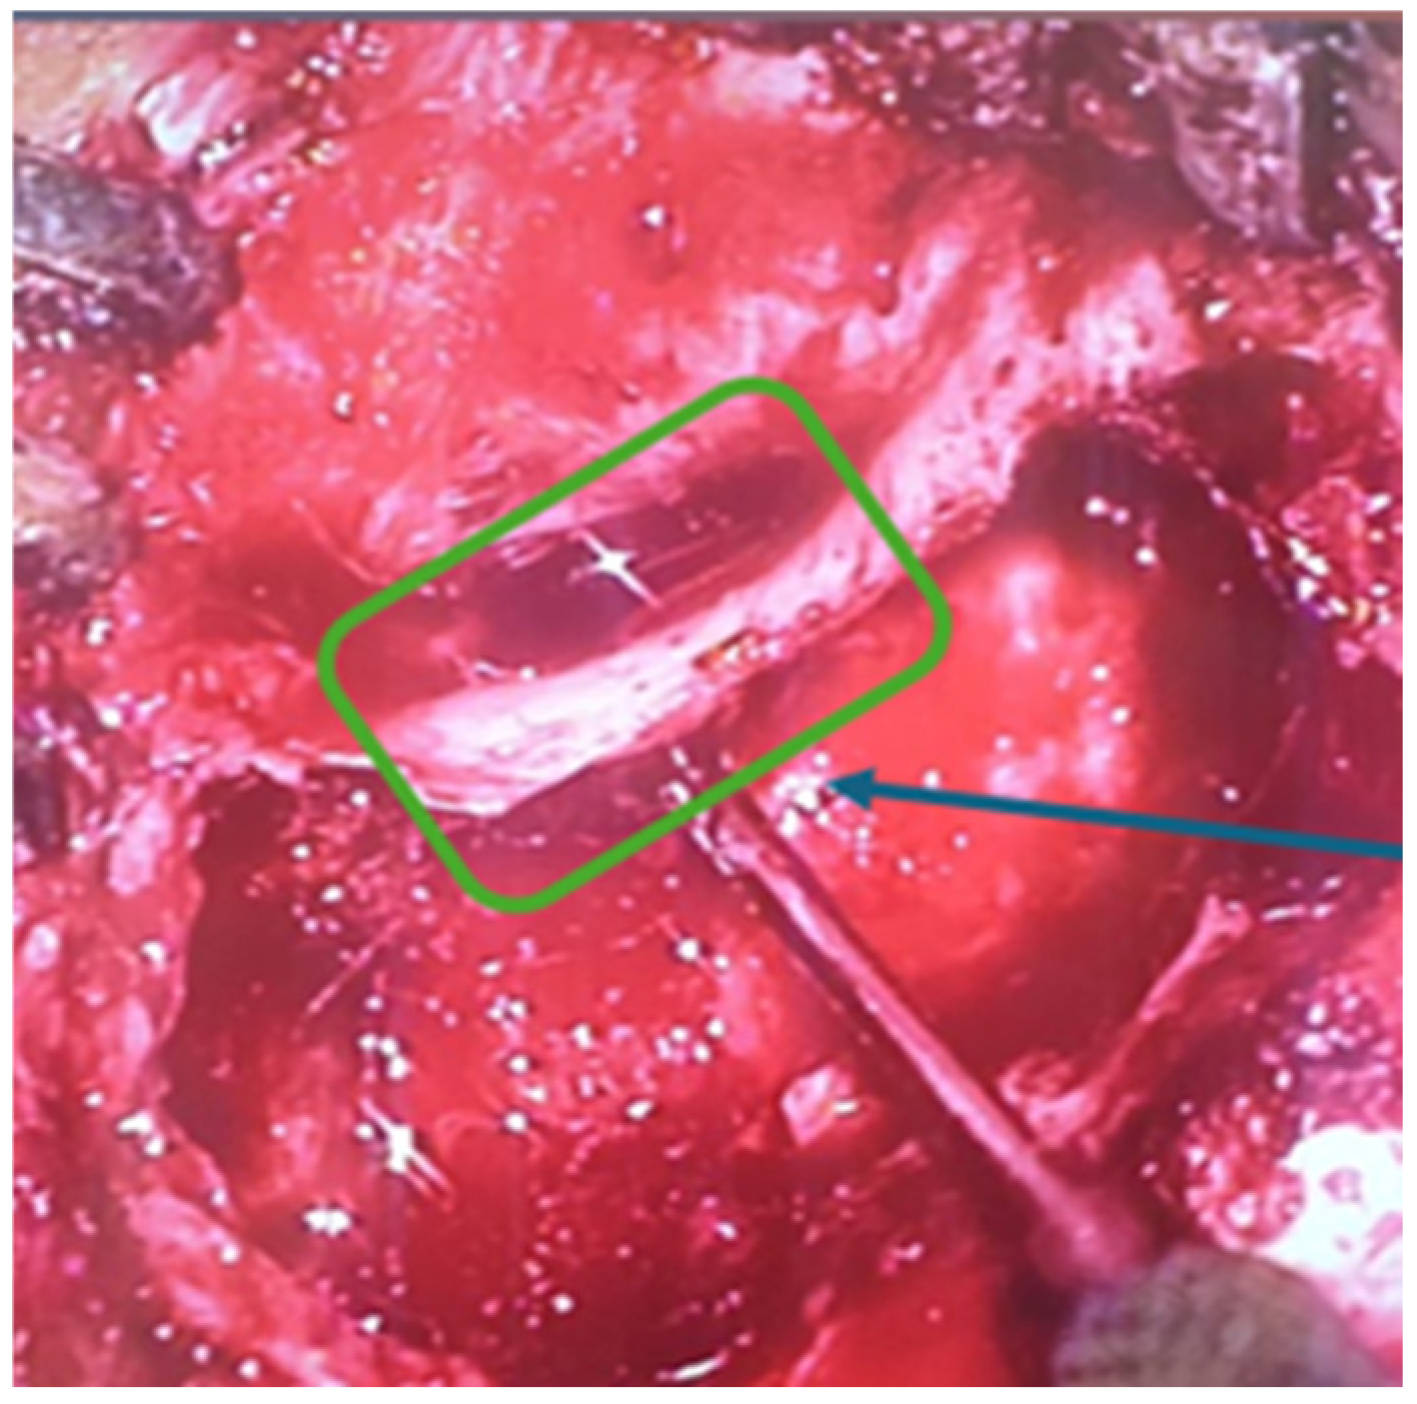

A surgical intervention was performed—radical trepanation. It started with retroauricular incision and mastoid bone exposure. As we started drilling of the mastoid bone, there was a destruction of the normal mastoid bone structure by a soft tissue mass, which was filling the entire mastoid beneath the cortex. The aditus was also blocked by that soft tissue. Following the destruction in a cranial direction, there was a 3 cm zone of exposed durra matter (Figure 4). After removing of the posterior wall of the external auditory channel, there was a large defect (Figure 5), through which the soft tissue was spreading from the mastoid to the external auditory channel. Step by step a classical radical trepanation cavity was formed. Tympanic membrane and ossicular chain remnants were visualized and removed. During the inspection of the tympanic cavity, a small tumour mass, which causes profuse bleeding if touched, was found in the area of the Eustachian tube hole. Intraoperative frozen section biopsies of the other soft tissue masses were all negative for malignant tumour cells and because of that, a decision for postoperative MRI around 30 days after the surgery was taken to clarify the surgical finding.

Figure 4. Exposed dura mater.

Figure 5. Dehiscence of the external auditory canal wall.